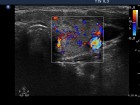

Follow-up examinations (rows from 1st to 8th):

Comments:

1. The patient initially presented with a large thyroid, therefore we suggested definitive therapy.

2. Note the relation between volume, echogenicity, vascularization and hormone levels.